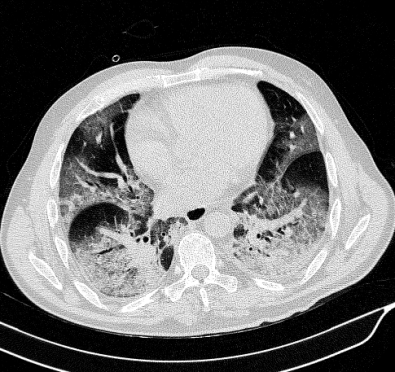

Lung segmentation results for the polymorphic and nonpolymorphic models are shown in Figure 3. Quantitative evaluation of lung segmentations was performed on CT images by comparing the segmentations to ground truth manual segmentations. The Dice coefficient was used to measure volume overlap and the average symmetric surface distance (ASSD) was used to assess boundary accuracy. The ASSD and Dice coefficient results for each of the four evaluation datasets are shown in Table 2. Overall, on the COVID-19 dataset the polymorphic model achieved an average ASSD of mm and average Dice coefficient of . By comparison, the nonpolymorphic model achieved an average ASSD of mm and average Dice coefficient of . ASSD and Dice coefficient results with respect to nonaerated lung volume fraction are displayed in Figure 4. Two-way analysis of variance revealed a significant interaction between model and nonaerated fraction for each evaluation metric, indicating that the regression coefficients with respect to nonaerated fraction were significantly different for polymorphic vs. nonpolymorphic models.

Lobar segmentation results for the proposed method and PTK are shown in Figure 5 for right lungs and Figure 6 for left lungs. For each image in the COVID-19 dataset (133 images in total), the lobar segmentation result was used to extract the amount of poor aeration () and consolidation () in each lobe. Common phenotypes of COVID-19 affected lungs were identified by hierarchical clustering over the fraction of poorly aerated and consolidated tissue in each lobe. Dendrographic analysis in Figure 7 reveals four primary clusters of patients that were identified by the hierarchical clustering: (a) mild loss of aeration primarily in the two lower lobes without consolidation; (b) moderate loss of aeration focused in the two lower lobes with or without consolidation in lower lobes; (c) severe loss of aeration throughout all lobes with or without consolidation; and (d) severe loss of aeration and consolidation throughout all lobes.